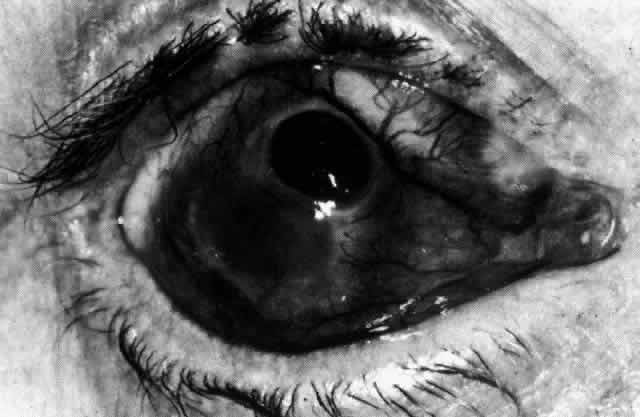

The object of slit lamp examination is to determine the depth and nature of scleral and episcleral conditions and the presence of corneal changes. The changes seen are drawn in the records. With the use of diffuse light with a neutral density filter, the vascular networks of both eyes are examined in detail to determine the layer in which the vessels show maximum congestion, the infiltration of episcleral tissues, and the edema of sclera, episclera, or subconjunctival space. Slit lamp examination is also used to ascertain the nature and depth of any corneal changes; the presence of scleral edema (for which it may be necessary to blanch the superficial tissues with epinephrine 1:1000 or phenylephrine 10%); the nature of any episcleral infiltration or mass; and the presence of cells in the anterior chamber or vitreous and posterior synechiae. The red-free (green) filter is extremely valuable in confirming the areas of maximum congestion and whether any areas are totally avascular. Because this is an important physical sign and is easily missed, examination in red-free light should be routinely performed. The green light brings the vessels into very sharp contrast with the background and enables the position of maximum inflammation to be determined with certainty. It also enables the paths and configurations of the vessels to be followed and will show lymphocytic infiltration of the episcleral tissue as yellow spots; this often indicates that the condition is more extensive than previously supposed (Fig. 8).

Fig. 8. Examination in red-free light. Blood vessels brought into sharp contrast reveal areas of lymphocytic infiltration in episcleral tissues, in this case due to herpes simplex virus.